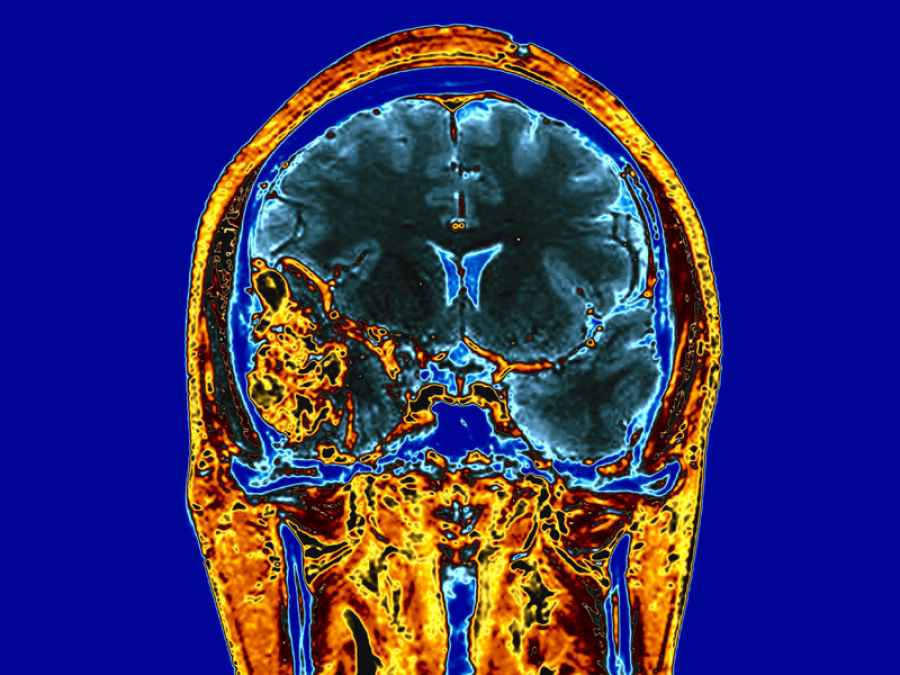

El gadolinio, que se usa como medio de contraste en las resonancias magnéticas, si se reparte dentro de las células cancerígenas podría acabar con ellas mediante la liberación de electrones tras ser golpeadas por rayos X, según una investigación publicada en la revista ‘Scientific Reports’ y cuyo objetivo es buscar la manera en que la radioterapia solo actúe sobre las células cancerosas.